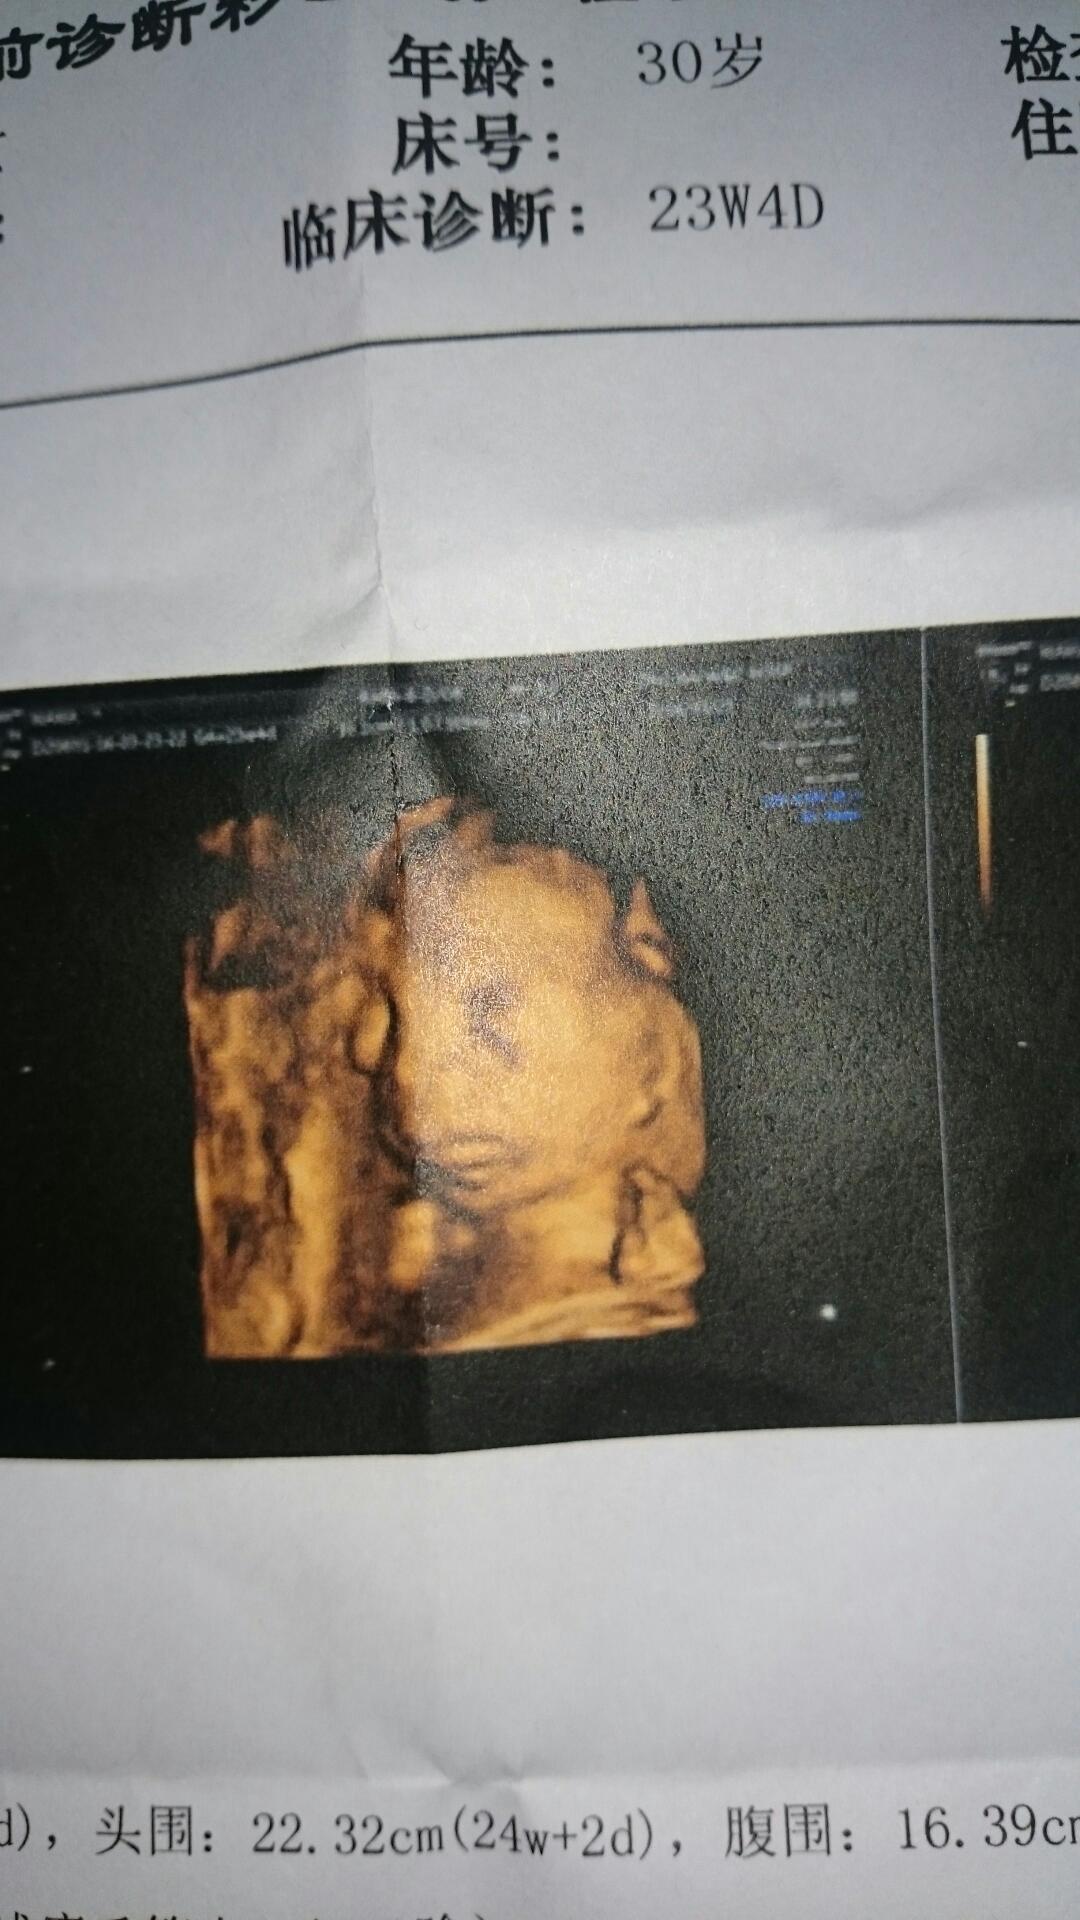

六个月了,被照出胎儿畸形,犹如晴天霹雳

3月23号,今天的日子永远记得,26号就六个月了,照三维既然被查出宝贝手臂畸形,老公是军人,为了这个小孩吃尽了苦头,好不容易怀上了,既然…亲团…蛋狗套老天为什么要这耀亲样子对待我,我到底该怎么办……

哪里畸形了?这不是很好么?

宝宝的手,没有肱骨,直接搭在肩膀上的

臭臭和胖胖01:哪里畸形了?这不是很好么?

看起来好好的,是不是看不清,宝妈要慎重啊。

已经去两家医院检查了,都是有权威的医院,都是一样的结果[泪][泪][泪][泪]